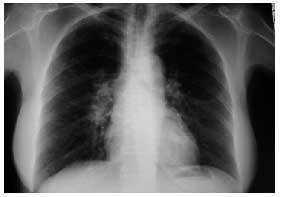

Figura 1. Radiografía de tórax PA: adenopatías hiliares derechas.

Caso clínico. Mujer de 59 años, sin antecedentes personales de interés, que acudió a la consulta por presentar un cuadro de astenia y artralgias generalizadas de dos semanas de evolución. En la exploración física se objetiva artritis bilateral de MCF y de rodillas. Ante la sospecha de enfermedad reumática se solicitaron hemograma, PCR, FR y ANAS, que fueron normales, encontrándose una VSG de 55 y en la bioquímica un patrón de colestasis disociada con GOT de 81, GPT de 127, GGT de 132 y FA de 680, por lo que se realizaron serologías a VHA, VHB y VHC y eco abdominal, con resultados normales. Dos semanas después, la paciente presentaba dos nuevos síntomas: tos seca y febrícula vespertina, y en la exploración física destacaban nódulos subcutáneos (de 2 × 2 cm de diámetro) dolorosos a la palpación en ambas piernas, por lo que se solicitó una radiografía de tórax que demostró adenopatías hiliares derechas (figs. 1 y 2). Se planteó el diagnóstico diferencial entre tuberculosis, sarcoidosis y linfoma, y la paciente fue remitida al hospital de referencia para continuar el estudio. Se realizaron un test de Mantoux, que fue negativo, y una TAC torácica en la que se objetivaron adenopatías hiliares bilaterales y mediastínicas, sin alteraciones parenquimatosas ni pleurales. Posteriormente se realizó una biopsia hepática, con el resultado de granulomatosis epitelioide no necrosante. La exploración oftalmológica, la biopsia de los nódulos subcutáneos y la gammagrafía pulmonar fueron normales. Se estableció el diagnóstico de sarcoidosis aguda con afección ganglionar mediastínica e hiliar, hepática y cutánea (eritema nudoso). La paciente fue tratada con prednisona, 30 mg cada 12 horas durante 15 días y posteriormente en pauta descendente. La paciente evoluciona de manera favorable, quedando asintomática tras el tratamiento. En la revisión a los 6 meses del inicio del cuadro, sigue asintomática, apreciándose una mejoría de la colestasis disociada y disminución de las adenopatías hiliares.